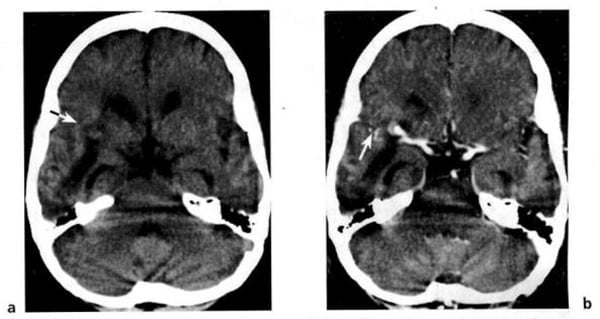

Hình 1.41. Nhồi máu não ở tay sau của bao trong bên phải. Vài giờ sau khi xuất hiện triệu chứng của đột quỵ. XQCLĐT (a) âm tính. Sáu ngày sau (b), tổn thương mật độ thấp hiện rõ. Do kích thước nhỏ, hiệu ứng choán chỗ không đáng kể.